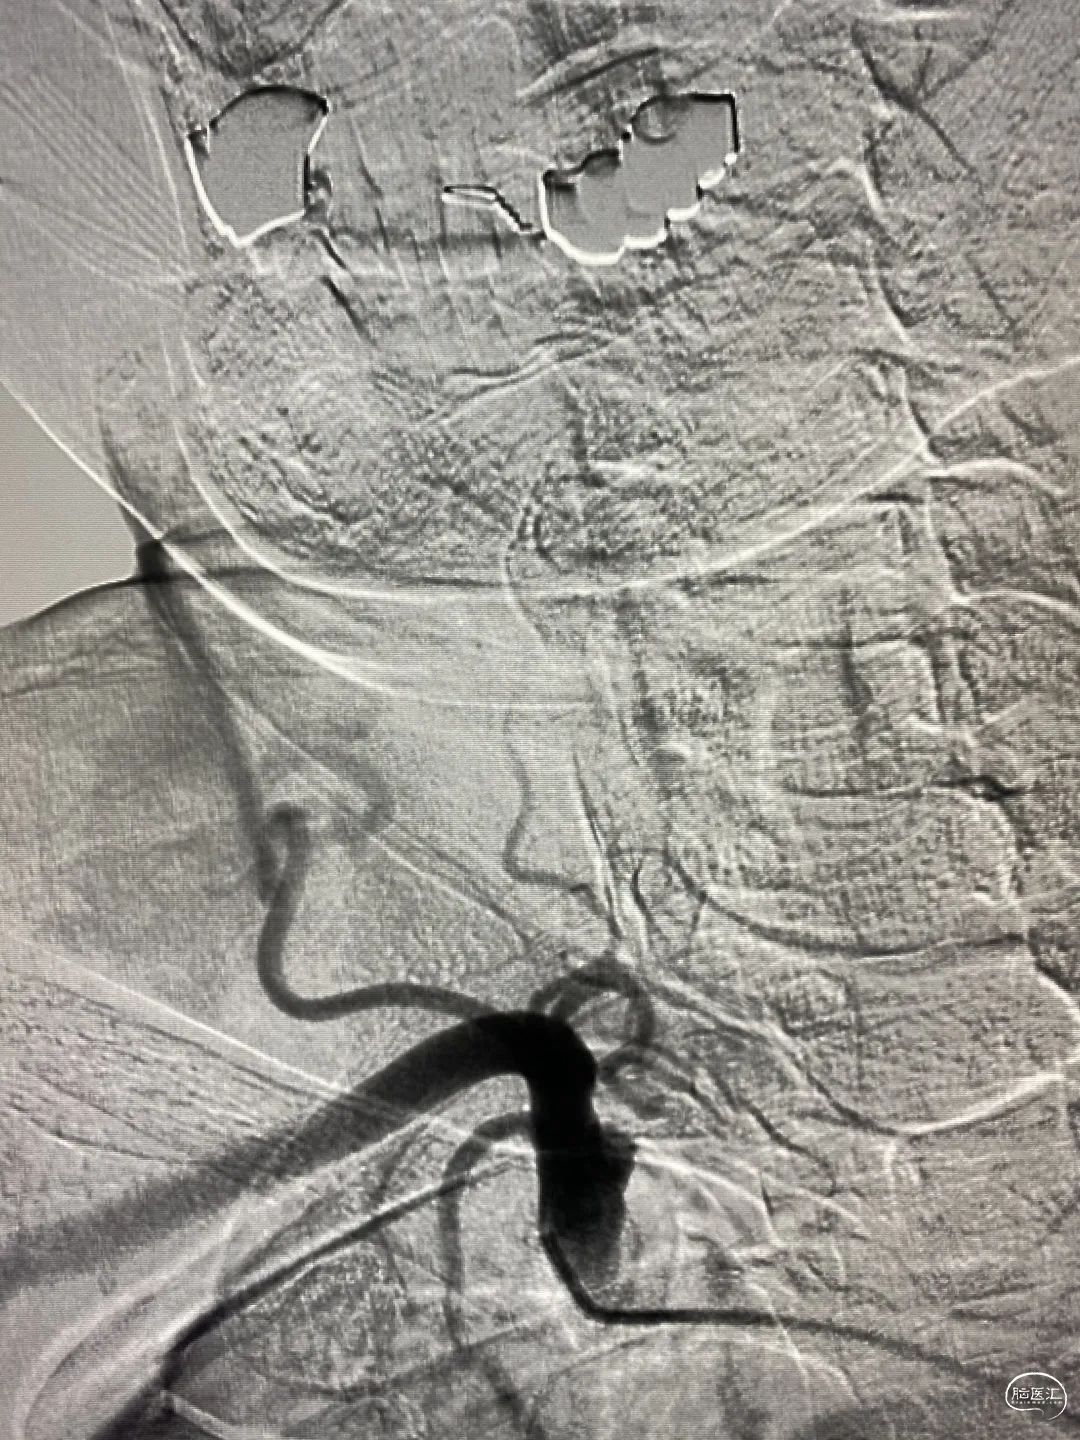

全脑血管造影示:左侧椎动脉。

DSA:

左侧椎基底动脉交界处夹层动脉瘤,大小12.9mm×12.5mm×8.75mm瘤颈累及整个载瘤动脉,载瘤动脉远端血管直径2.8mm,基底动脉中段夹层动脉瘤,右侧椎动脉闭塞。

右侧股动脉穿刺,右侧6F股动脉鞘+6F导引导管,到达左侧椎动脉V4段;选择合适的角度造影,Prowler Select Plus到达基底动脉远端,测量尺寸,选择合适的支架型号弹簧圈微导管由左侧椎动脉置入动脉瘤瘤腔。

弹簧圈部分释放,植入Enterprise 4.5mm×28mm覆盖责任动脉瘤瘤颈,后填塞弹簧圈,支架保护载瘤动脉欠佳。

给予部分回收弹簧圈,赛诺Neuro LPS™颅内低压球囊到位支架内,命名压力充盈球囊保持支架稳定性,防止支架塌陷保护载瘤动脉。

重复上述过程,继续送入6枚弹簧圈,造影显示动脉瘤栓塞完全载瘤动脉通畅。

为减少复发概率给予第二枚EP支架叠加。

载瘤动脉近端支架覆盖处狭窄,给予赛诺Neuro LPS™颅内低压球囊后扩。

动脉瘤填塞致密,载瘤动脉通畅,小脑后下动脉血流通畅。